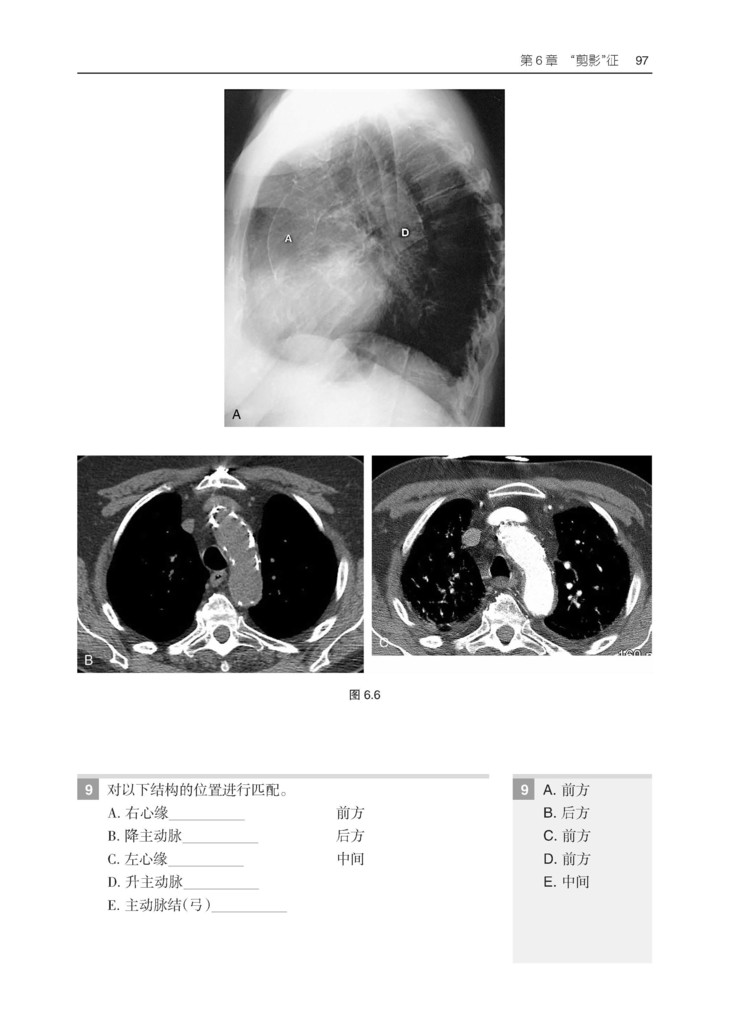

本书易于阅读、引人入胜,长期以来一直是广大放射科医学生和医生的首选学习资源。本书提供了有关胸部影像学方面的所有内容,包括病理学和解剖学难题,以通俗易懂的方式对基础理论、影像判读方法和专业术语进行了阐释。紧跟学科前沿,包括胸膜肺实质纤维弹性组织增生症、合并肺纤维化与肺气肿、与年龄相关的肺部变化、间质性肺病、肺癌筛查和肿瘤分类,以及降低辐射剂量和安全考虑等热点话题。

3.包含550 余幅高质量影像图片,并根据需要配有相关的PET、CT 和 MRI 图像。